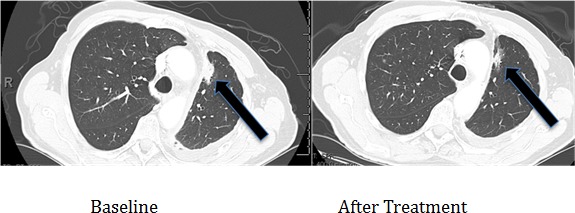

Three patients with known EGFR-(reversible TKI) resistant mutations (two with insertions in exon 20 (Table 2, Cases 1 and 2) and one with an exon 20 T790M mutation (Case 3) were treated with an EGFR antibody (cetuximab)-based regimen. Both patients with insertions in exon 20 achieved durable partial remissions consistent with the predictions from our structural modeling (Table 2, Figures 7 and 8). The third patient, having the exon 19 (LREA-type) mutation, initially responded to the reversible TKI inhibitor erlotinib (partial remission for 17 months); at the time that the T790M was detected, the patient failed to respond to erlotinib combined with cetuximab, again consistent with the molecular structure predictions.

| 2 | 38/Male/Asian | Adenocarcinoma of the lung with bone metastases | No | D770_P772del_insKG in exon 20 | Unknown | Partial response, still progression free at 6 months (Figure 8) | Received cetuximab with chemotherapy and bevacizumab |

Figure 8. Computerized tomographic scan of the lungs of Patient #2 (Table 2) with EGFR exon 20 aberration D770_P772del_insKG before and after treatment with a cetuximab-based regimen shows tumor regression.

Of interest in this regard, we report three patients treated with EGFR antibody cetuximab-based regimens (Table 2). Two of these patients had mutations considered resistant to EGFR TKI inhibitors (D770>GY and D770_P772delsinKG (both in exon 20)), yet attained partial remissions on cetuximab-based therapy (Figures 7 and 8). One patient continues to do well on treatment for over 3.5 years (Table 2, Patient #1, and Figure 7). In contrast, a patient with the exon 20 T790M EGFR-TKI resistant mutation (in addition to the exon 19 sensitive LREAdel aberration) did not respond to the combination of cetuximab and erlotinib (Table 2, Patient #3). Typically, these patients present with the sensitive EGFR LREAdel aberrations and initially respond to reversible TKIs such as erlotinib (and, a salutary effect of erlotinib was indeed seen in our patient early in the disease course), but the resistant T790M mutation then emerges [4]. Similarly Janjigian and colleagues failed to show activity for the erlotinib/cetuximab combination in patients with NSCLC and acquired resistance to erlotinib due to T790M mutations [25]. Our clinical observations are supported by the in silico modeling data (Figures 1 and 5), which demonstrate that exon 20 insertion aberrations would be expected to increase the attractive electrostatic dimerization energies, and such a change could be predicted to predispose to response to an EGFR antibody that attenuates or interferes with dimerization. Further, our modeling suggests that the LREA mutation can react to the combination of cetuximab and erlotinib, but the combination of LREA and T790M mutations can compromise this effect because of resistance of T790M mutant to TKI. Although there are limitations to this study, e.g., the small number of patients and the fact that the responders received combination therapy, the expected rate of response to the other drugs in the combination is low. These data suggest that some patients with gefitinib/erlotinib-resistant EGFR mutations, especially those in the amino acid 770 region of exon 20, may benefit from therapy with EGFR antibodies.